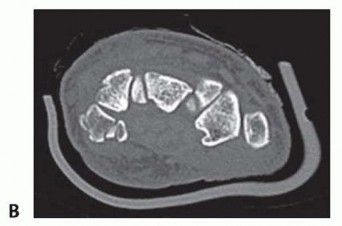

Despite optimal plain radiography, advanced imaging is frequently required. High-resolution computed tomography (CT) scanning with fine axial, coronal, and sagittal reconstructions has become the gold standard and the imaging modality of choice for complex carpal trauma. CT scans definitively confirm occult fractures, delineate intra-articular comminution, and reveal subtle associated injuries missed on plain films. They allow the surgeon to mentally construct a 3D model of the fracture, facilitating precise preoperative templating of screw trajectories and implant sizes. If dynamic instability is suspected but unconfirmed, an Examination Under Anesthesia (EUA) combined with real-time fluoroscopy (utilizing stress and distraction views) is performed immediately prior to the definitive procedure to finalize the surgical blueprint.